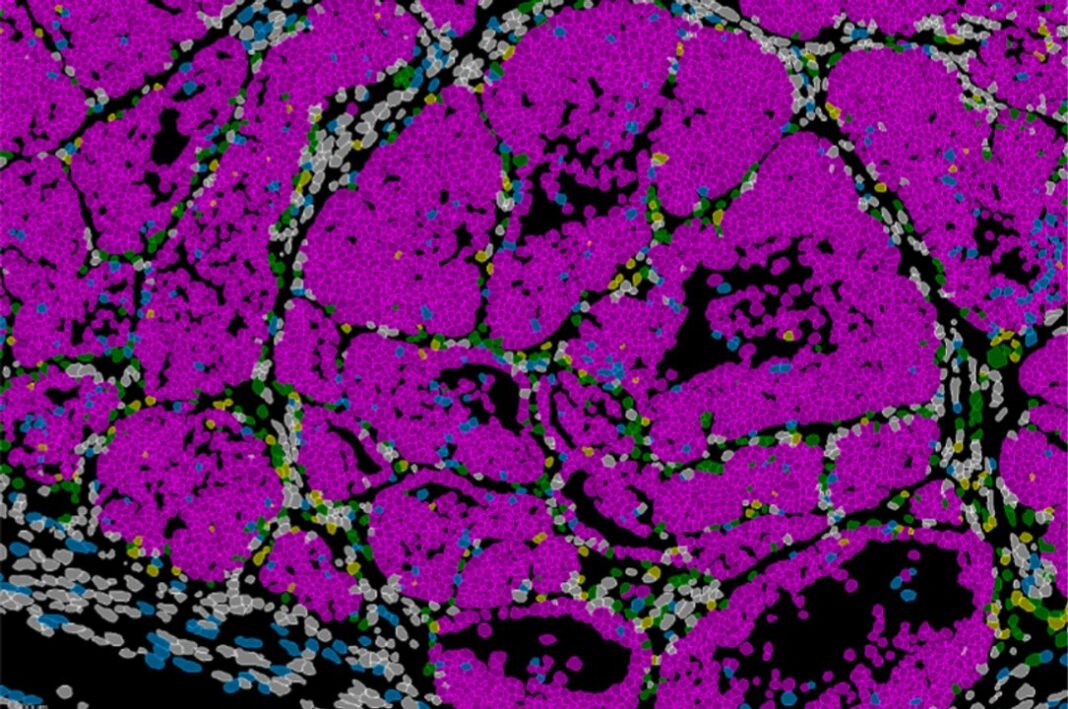

El equipo combinó modelos genéticos en ratón, análisis de célula única, estudios de cromatina y técnicas de transcriptómica espacial que permiten observar la organización y el comportamiento de las células directamente en el tejido tumoral.

De esa manera, los investigadores analizaron muestras de pacientes con cáncer de mama y detectaron patrones similares de expresión de Prrx1, lo que sugiere que el mecanismo descrito podría tener una relevancia directa en la clasificación y el pronóstico clínico.